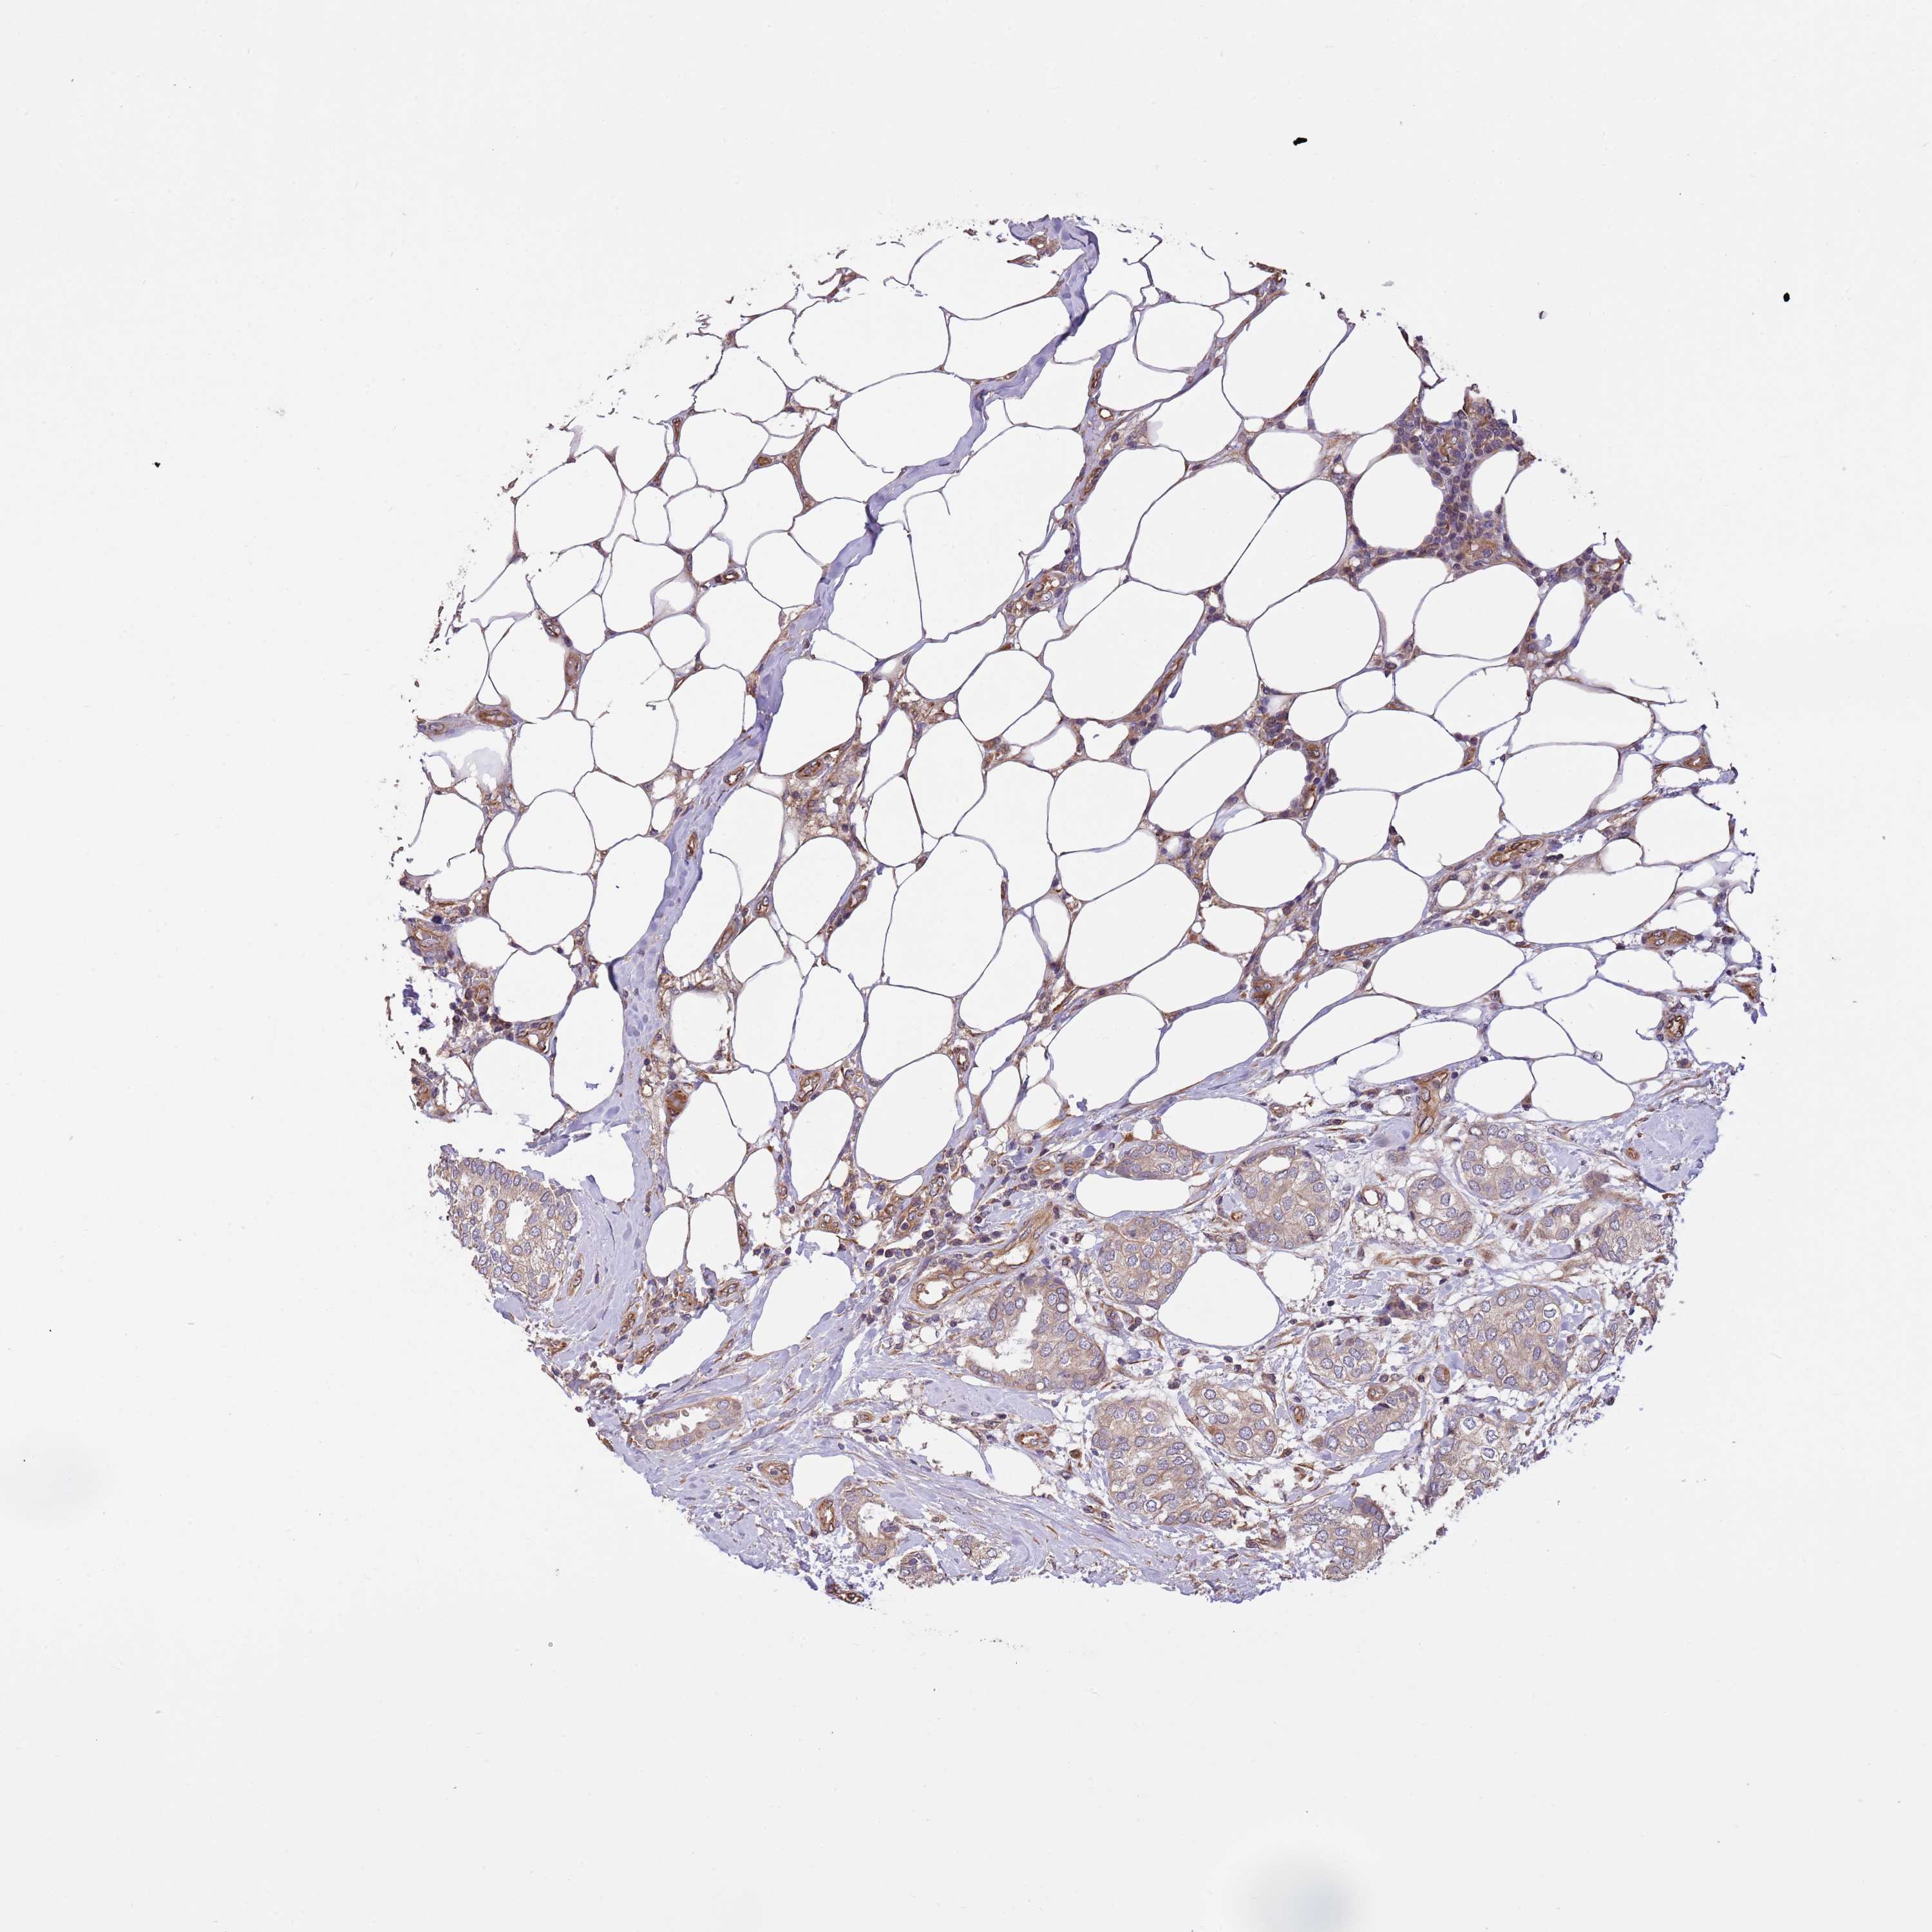

CANCER BREAST CANCER Show tissue menu

BRCA TCGA BRCA VALIDATION PROTEIN EXPRESSION

Breast cancer

Human cancer

Breast invasive carcinoma